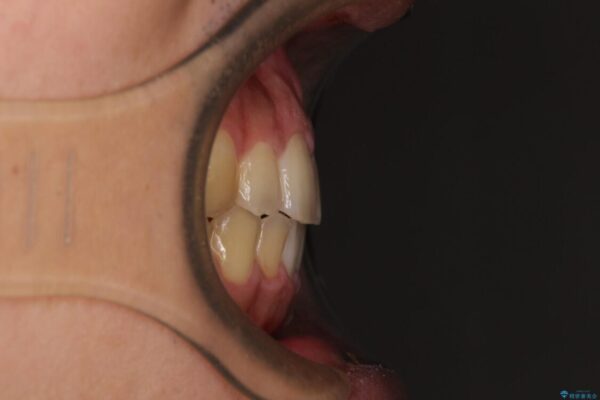

治療前

• 後戻りでデコボコの前歯 インビザライン矯正治療 治療前画像